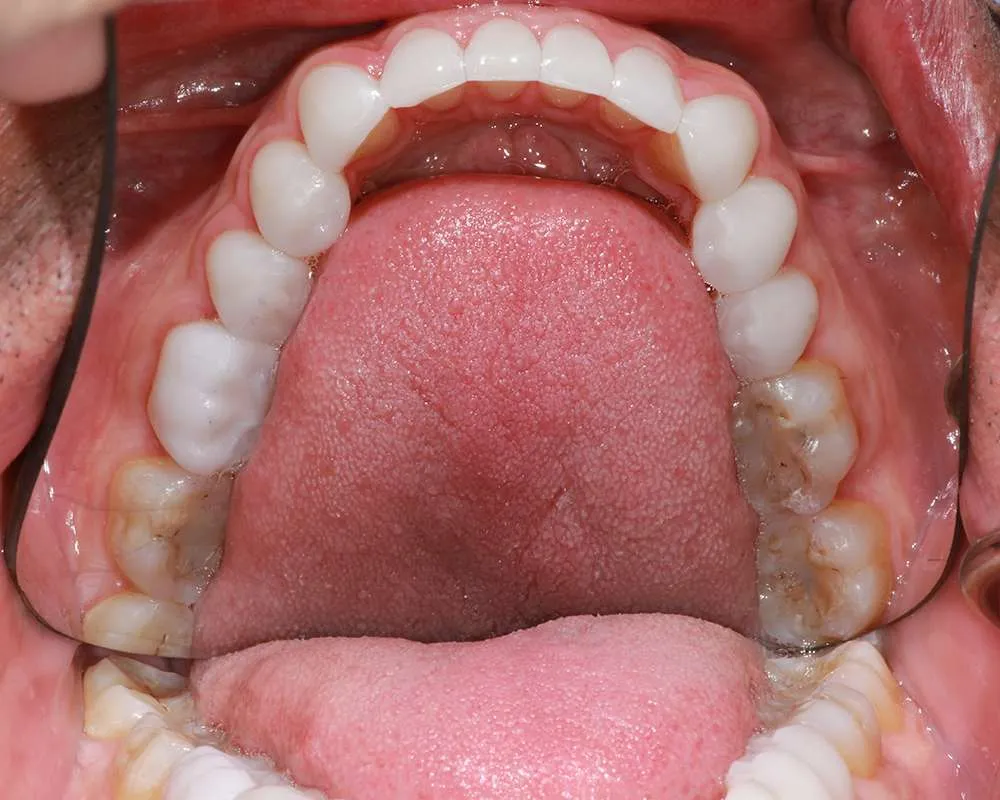

Real Stories, Real Results: Case Studies Showcasing How Our Personalized Approach Transforms Smiles and Lives

Complex Cases

Witness the Remarkable Changes We Can Achieve